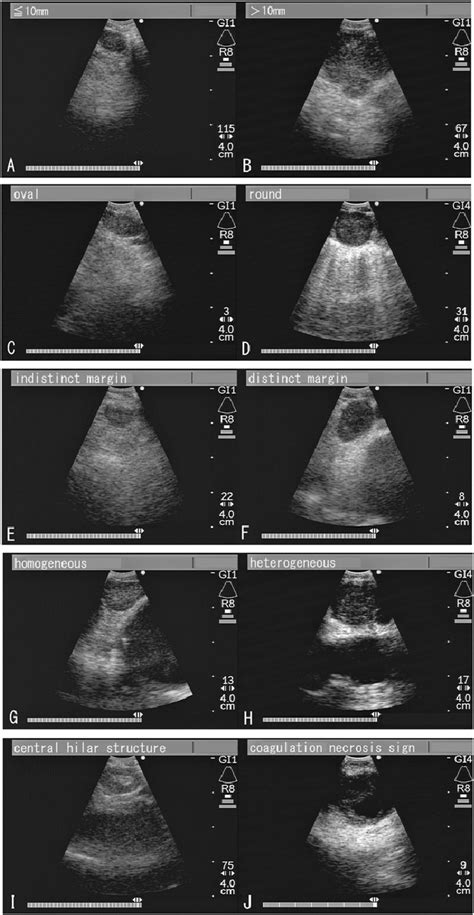

EBUS is primarily utilized for the diagnosis and staging of lung cancer, particularly for assessing mediastinal and hilar lymph nodes. The procedure involves the insertion of a flexible bronchoscope, equipped with an ultrasound probe at its tip, through the mouth or nose into the lungs. This allows for the examination of the airway walls and parabronchial structures. The ultrasound component provides high-resolution images that help in identifying abnormalities, such as enlarged lymph nodes, which can then be sampled for cytological examination using fine-needle aspiration (FNA) under real-time ultrasound guidance.

The technical specifications of EBUS equipment include high-frequency ultrasound probes that operate within the range of 5-12 MHz, providing detailed images of the structures surrounding the airways. The procedure is typically performed under conscious sedation or general anesthesia, ensuring patient comfort. During the procedure, the physician navigates the bronchoscope to the target area, uses the ultrasound to locate the lymph nodes or lesions of interest, and then performs FNA to collect tissue samples for pathological examination. The samples are then analyzed to determine the presence of cancer cells, which aids in diagnosing and staging the disease.